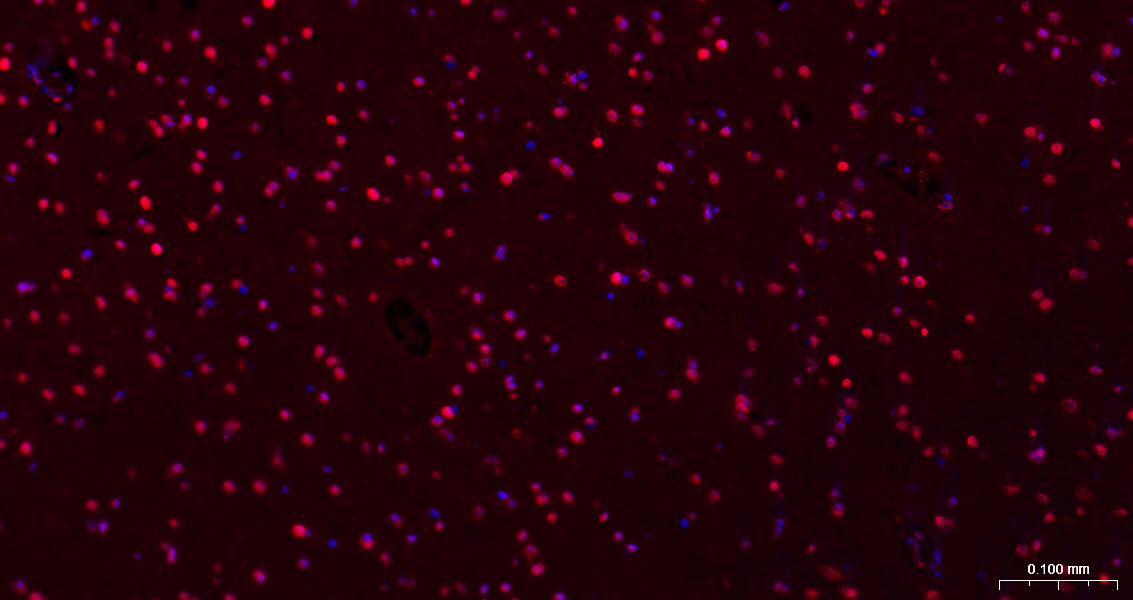

Paraformaldehyde-fixed, paraffin embedded Rat Cerebrum; Antigen retrieval by boiling in sodium citrate buffer (pH6.0) for 15 min; The section was incubated with HES1 Monoclonal Antibody, Unconjugated (bsm-52568R) at 1:200 overnight at 4°C. Followed by conjugated Goat Anti-Rabbit IgG antibody (Red, bs-0295G-BF594), DAPI (blue, C02-04002) was used to stain the cell nuclei.